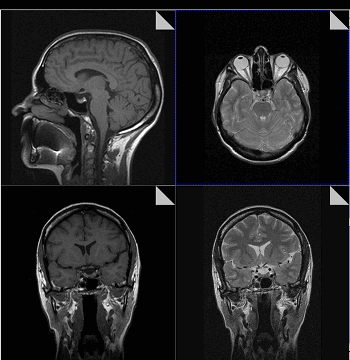

Плюсы: на МРТ хорошо видны хрящи, мягкие ткани, мозг; сканирование безвредно для беременных женщин и детей, можно делать хоть каждый день.

Минусы: занимает много времени, может спровоцировать приступ клаустрофобии (но есть томографы открытого типа, которые облегчают положение больного и подходят в том числе и для людей с ожирением). МРТ противопоказана людям с вживленными в тело электроприборами, например, кардиостимуляторами, и металлическими имплантатами. Впрочем, при некоторых условиях это ограничение можно обойти .

Когда назначают: при травмах, опухолях, аномалиях развития сосудов, заболеваниях спинного и головного мозга, суставов, органов малого таза.

В основе МРТ лежит явление магнитного резонанса, основанного на переизлучении радиоволн, взаимодействующих с атомами водорода, в избытке содержащимися в организме человека. Эти переизлученные электромагнитные волны улавливаются датчиком МР-томографа, усиливаются и в виде цифровых изображений появляются на экране монитора. Это безвредный и абсолютно безопасный для здоровья человека метод лучевой диагностики, так как в основе получения изображения отсутствует рентгеновское излучение, поэтому МРТ можно проходить неограниченное количество раз, с любым интервалом.

Существенное преимущество МР-томографии перед КТ заключается в том, что она не противопоказана беременным во II и III триместре и совершенно безопасна для детей. В МРТ исследуемая область сканируется в трех проекциях, что позволяет врачу-рентгенологу в полной мере оценить состояние тканей и органов исследуемой области, а высокая контрастность изображения и пространственное разрешение позволяют визуализировать серое и белое вещество головного мозга, оценивать состояние костного мозга и мягких тканей различной локализации. Кроме того, метод МРТ позволяет получать изображения сосудов головного мозга и сосудов шеи без введения контрастного препарата.

Конечно, как и многие другие методы исследования, МР-томография имеет ряд противопоказаний. Однако, если внимательно ознакомиться с ними, можно заметить, что в основном они связаны с наличием металлсодержащих имплантов (не обладающие магнитными свойствами устройства противопоказанием не являются), а также с выраженной клаустрофобией. Таким образом, в большинстве случаев МРТ может стать наиболее оптимальной и совершенно безопасной альтернативой компьютерной томографии и рентгенографии.